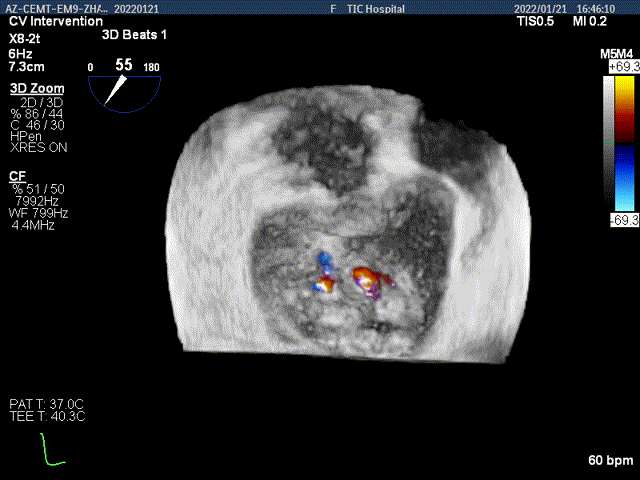

3D-color MV view:大量反流,起源于2区

Color-view:大量反流,主要血流PISA来源于2区

患者麻醉方式为全麻,建立静脉通路后,穿刺右侧股静脉,预埋ProGlide缝合器,食道超声指导下房间隔穿刺成功,将Superstiff导丝送至左房,应用18F鞘管扩张穿刺部位,沿导丝将导引导管送入左房,经导管鞘系统将NovoClasp瓣膜夹顺利到达二尖瓣目标位置,在食道超声辅助下,将成形夹精确定位后,使用1个宽的clip(MCD0101)成功夹合二尖瓣A2-P2区,彩色多普勒超声(2D+3D)显示微少量残余分流,整体反流量改善2级以上,后多切面证实夹合组织充分,肺静脉多普勒波形由反向恢复正常,手术顺利结束,安返普通病房。